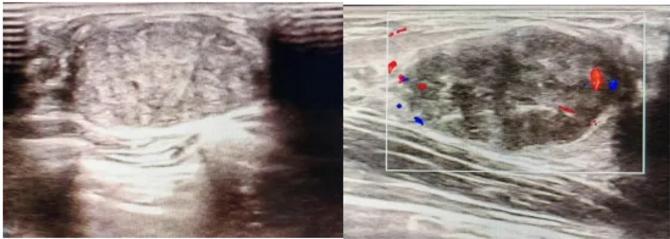

三、彩超檢查:無(wú)創(chuàng)檢查的“黃金眼”

高分辨率:可清晰顯示腫塊形態(tài)、血流信號(hào),敏感度達(dá)80%-90%。

2.彩超報(bào)告關(guān)鍵指標(biāo)

形態(tài):良性多呈橢圓形或分葉狀,邊界光滑。

縱橫比: 良性通常<1(橫徑>縱徑) 。

血流信號(hào):纖維瘤血流較少,惡性常伴豐富雜亂血流。

鈣化:粗大鈣化多為良性,細(xì)小簇狀鈣化需警惕惡性。

BI-RADS分級(jí):2-3類提示良性,4類以上需進(jìn)一步檢查。

典型表現(xiàn):

橢圓形低回聲團(tuán)塊,包膜完整,內(nèi)部回聲均勻,后方回聲增強(qiáng),周邊無(wú)“蟹足樣”浸潤(rùn)。